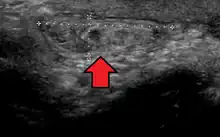

In the diagnosis of abdominal hernias, imaging is the principal means of detecting internal diaphragmatic and other nonpalpable or unsuspected hernias. Multidetector CT (MDCT) can show with precision the anatomic site of the hernia sac, the contents of the sac, and any complications. MDCT also offers clear detail of the abdominal wall allowing wall hernias to be identified accurately.[19]